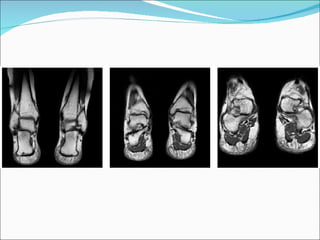

TDM  La technique d’examen repose sur la « règle des deux ». –  Deux pieds. Le scanner permet une étude bilatérale et comparative des pieds et des chevilles placés côte à côte, le plus symétriquement possible. –  Deux plans de coupes. –  Le plan verticofrontal, perpendiculaire à la plante du pied, est riche d’informations. Il analyse bien les joues et le dôme du talus, le calcanéus, l’articulation sous-talienne, la concavité de l’arche médiale, l’articulation de Lisfranc. Le patient est placé en décubitus dorsal, les genoux fléchis et calés par un coussin mousse, les chevilles en flexion plantaire, les deux pieds à plat de façon exactement symétrique.

TDM –  Un deuxième plan, horizontal, parallèle à la plante du pied, permet une bonne étude des ligaments des articulations tibiotarsienne et de Chopart. Le patient est en décubitus dorsal, plantes des pieds perpendiculaires à la table, bien symétriques et calées par un support dur vertical. un filtre de convolution plutôt dur, une matrice élevée (512 ´ 512). Ces coupes parasagittales sont très intéressantes dans l’étude de l’articulation sous-talienne et de la plante du pied et peuvent alors être obtenues à partir d’une seule acquisition volumique en mode hélicoïdal (coupes millimétriques jointives pitchées, reconstruites tous les 0,7 mm), avec reconstructions 2D multiplanaires ou 3 D. –  Deux fenêtres. l’une étudiant l’os : 200 à 300 UH de hauteur, 1 500/2 000 UH de largeur ; l’autre les parties molles : 0 à 50 UH de hauteur, 300/400 UH de largeur.

TDM étudie très bien le squelette, surtout reconstructions planes et tridimensionnelles rapides Médiocre résolution en densité    différencie mal les structures dont les densités sont voisines de celle de l’eau : l’œdème, les épanchements, les tissus inflammatoires, le cartilage..., d’où la fréquente nécessité d’utiliser un produit de contraste iodé, injecté en intra-articulaire ou en péritendineux, plus rarement en intraveineux, afin de renforcer artificiellement un contraste naturel trop faible.

arthroscanner Cet examen comporte une arthrographie simple de la cheville couplée à un scanner réalisé en coupes fines. juger du volume de la cavité articulaire, de sa morphologie et de ses limites. Le produit de contraste moule en particulier le cartilage articulaire et les limites de la capsule latérale et médiale.

IRM T1 pour son excellent rendu de l’anatomie T2 écho de spin rapide avec suppression du signal de la graisse (ou le STIR) pour son potentiel de mise en évidence de l’eau, surtout intraosseuse imagerie de la moelle osseuse (recherche d’un œdème, d’une inflammation...) et des tissus mous (tumeurs, tendinopathies, infections...)  Elle constitue un complément presque parfait du scanner

IRM Les séquences pondérées en T2 et les séquences T1 après injection de gadolinium sont réalisées préférentiellement en saturation de graisse. L’utilisation de gadolinium est nécessaire s’il existe une suspicion de pathologie tumorale ou infectieuse.